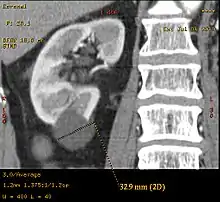

A very small (8 mm) simple renal cyst. Bosniak II cyst at the lower pole of right kidney with septations within.

Bosniak II cyst at the lower pole of right kidney with septations within.